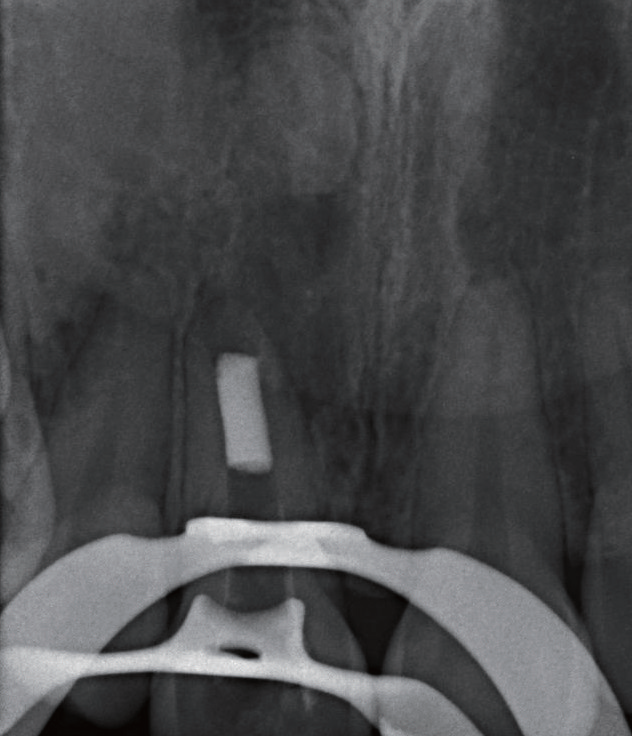

治疗过程   显微镜下可见11牙冠唇侧(图4)和腭侧(图5)存在数个大小深浅不一的裂纹,开髓至牙本质层(图6),患者表示无任何不适,开髓后就闻到髓腔内有臭味溢出,但患者依然无疼痛,经确认11牙髓已坏死(图7)。随后进行根管预备、次氯酸钠溶液冲洗、纸尖干燥(图8)、试主尖(图9),因根尖呈开口状,决定将牙胶尖四周覆盖MTA进行根尖封闭(图10~12),X线片显示根充密合,后续封闭根管中部和冠部(图13),并用光固化复合树脂充填11牙冠(图14),调磨抛光,再次拍摄根尖X线片确认治疗结果(图15),嘱患者定期复查,观察患牙。

图8 11根管预备后用牙胶尖探出根尖口,发现根尖病灶区里虽无脓液也无新鲜血液

图9 由于11 根尖未闭合,试主尖时始终得不到理想回拉阻力

图10 以自制MTA 覆满的牙胶尖,尝试封闭呈喇叭状开口的根尖

图11 运用施德氏根充法,将特制牙胶尖压实

图12 不断重复加热、软化覆满MTA 的牙胶尖,以垂直加压法将其填满根尖

图15 X 线片显示11 根充密合,同时根管中段牙冠部充填完好

预后   根管治疗后半年(图16)、两年半(图17~18)、三年半(图19)患者前来复诊,可见11根尖恢复良好,已完全愈合,随后进行全冠修复,完成患牙的全部治疗。

图16 根充半年后,患者自觉按压11 根部牙龈时,虽无不适但改善并不明显;X线片显示11 根尖放射性阴影边界变模糊,这是病灶开始愈合的表现

图18 根充两年半后,患者自觉按压和敲击11时无明显不适,X 线片显示原根尖骨组织缺损逐步愈合,可见根尖牙槽骨板重现

图19 根充三年半后,X 线片可见11 根尖牙槽骨板完整,覆盖突出的牙胶尖,原开口的根尖于治疗后已经闭合